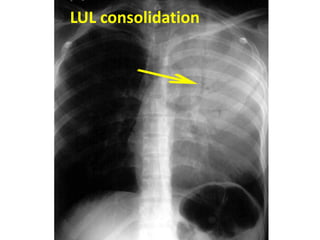

LUL consolidation